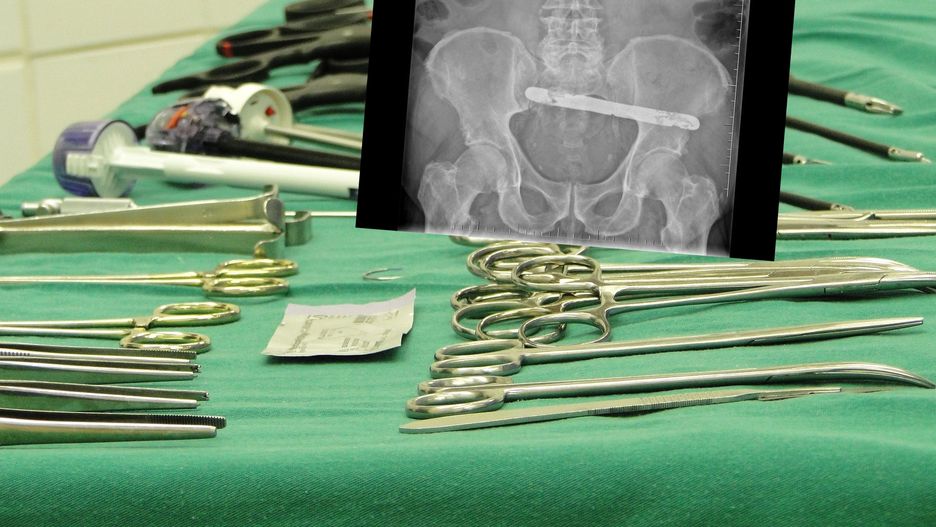

To narzędzie zostawiono w brzuchu pana Janusza po operacji

To narzędzie zostawiono w brzuchu pana Janusza po operacji © Archiwum Rzecznika Praw Pacjenta